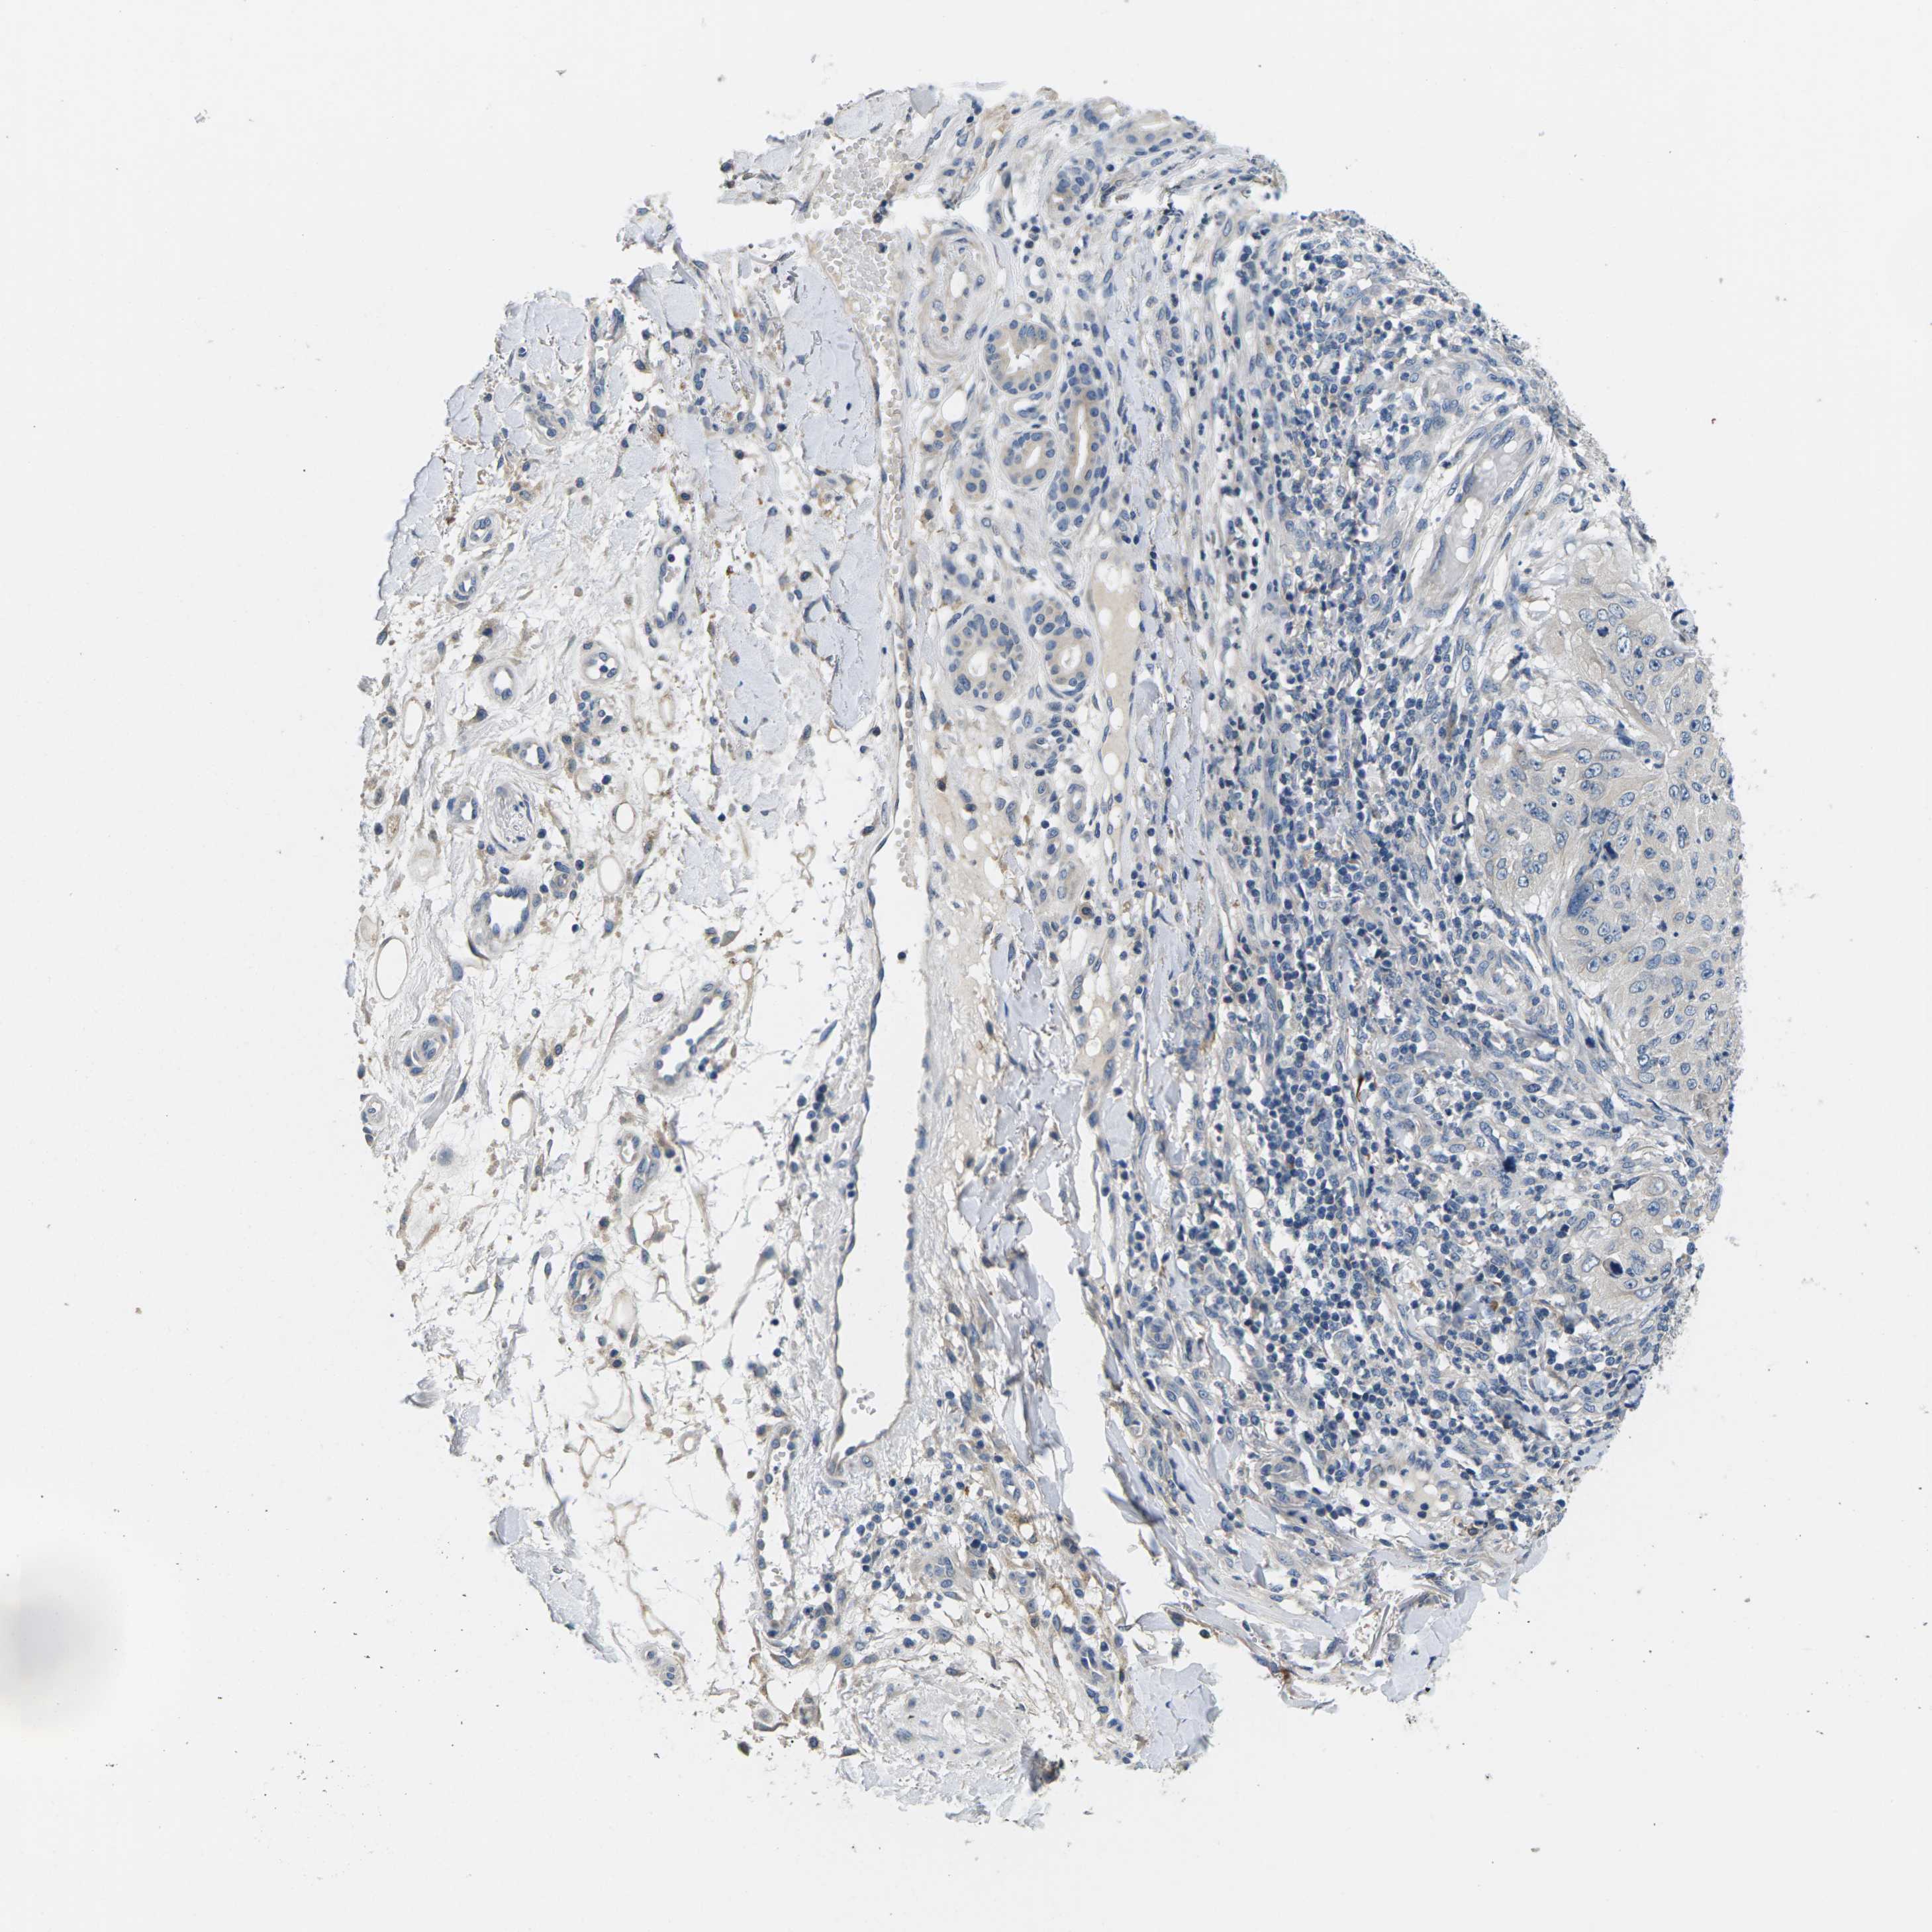

SKIN CANCER - Protein expressioni

A mouse-over function shows sample information and annotation data. Click on an image to view it in a full screen mode. Samples can be filtered based on level of antibody staining by selecting one or several of the following categories: high, medium, low and not detected. The assay and annotation is described here.

Antibody staining in the annotated cell types in the current human tissue is reported as not detected, low, medium, or high, based on conventional immunohistochemistry profiling in selected tissues. This score is based on the combination of the staining intensity and fraction of stained cells.

Each image is clickable and will lead to virtual microscopy that enables deeper exploration of all samples and also displays staining intensity scores, fraction scores and subcellular localization as well as patient and tissue information for each sample.

Antibody HPA015242

Squamous cell carcinoma, NOS

Squamous cell carcinoma, metastatic, NOS

Basal cell carcinoma